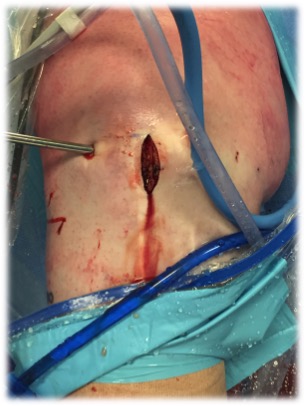

Small medial or lateral parapatella to make trough

- prepare meniscus

- leave margin of meniscus to allow suture to

- mark site with needle

- just on inner margin of articular surface

- mark with shaver

- insert guide pin, drill over, then insert box cutter

- carefully clean out with shaver